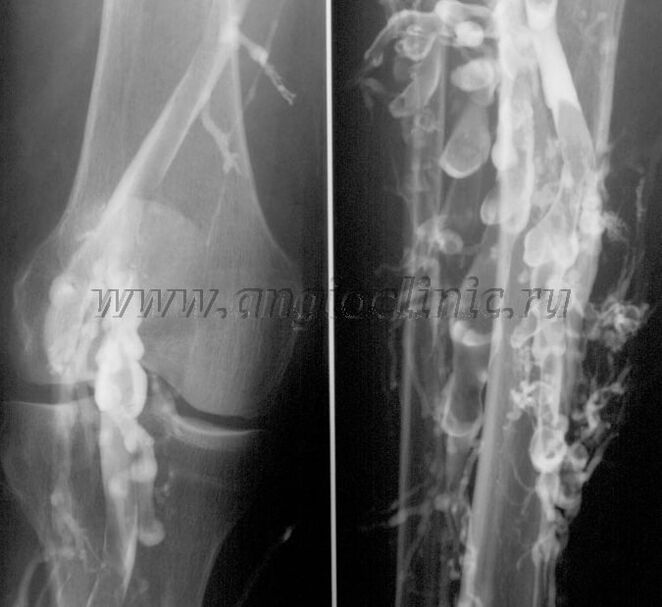

Venografía de contraste

Normalmente, a exploración de ultrasóns é suficiente para un diagnóstico completo da patoloxía venosa, pero nalgúns casos é necesario estudar a relación entre o estado do sistema venoso profundo e superficial, especialmente en caso de recaídas de varices e varices secundarias.

Para resolver estes problemas, utilízase un exame de raios X de contraste. Percónanse as veas safenas e adminístrase contraste. O movemento do contraste obsérvase no monitor da máquina de raios X e realízanse todas as probas e proxeccións necesarias. Actualmente, a venografía para varices úsase moi raramente.